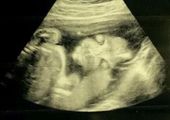

Niesamowite zdjęcia USG. Nawet lekarze byli zaskoczeni

Badanie USG to zwykle jeden z najbardziej wyczekiwanych momentów w czasie ciąży. Jesteśmy ciekawi, jak będzie wyglądać nasze dziecko, jaki będzie miało kształt nosa czy uszu. Czasem jednak zamiast radości, zdjęcie USG może stać się powodem niepokoju i stresu. Tak było w przypadku Jade Boyland z Somerset w południowo-zachodniej Anglii, która na swoim pierwszym badaniu USG ujrzała twarz swojego dziecka. Była przerażona, ponieważ zobaczyła zarys zgarbionego malucha, z wielkimi oczami i wydłużonymi palcami, które przypominały szpony. Jade przyznała, że gdy pierwszy raz zobaczyła twarz swojego malucha, nazwała "demonicznym dzieckiem". Początkowo żartowała z tego, jednak wraz z biegiem ciąży coraz bardziej przejmowała się kwestią wyglądu córki po porodzie. Niepokój jednak okazał się zbyteczny, ponieważ urodziła piękną, zdrową córeczkę, która obecnie ma 9 lat. Po "demonicznym wyglądzie" nie ma żadnego śladu. Jednak, jak twierdzi mama, córka ma "demoniczny charakter" i żartuje, że wiedziała to od pierwszego badania. Tak obecnie wygląda Lydia